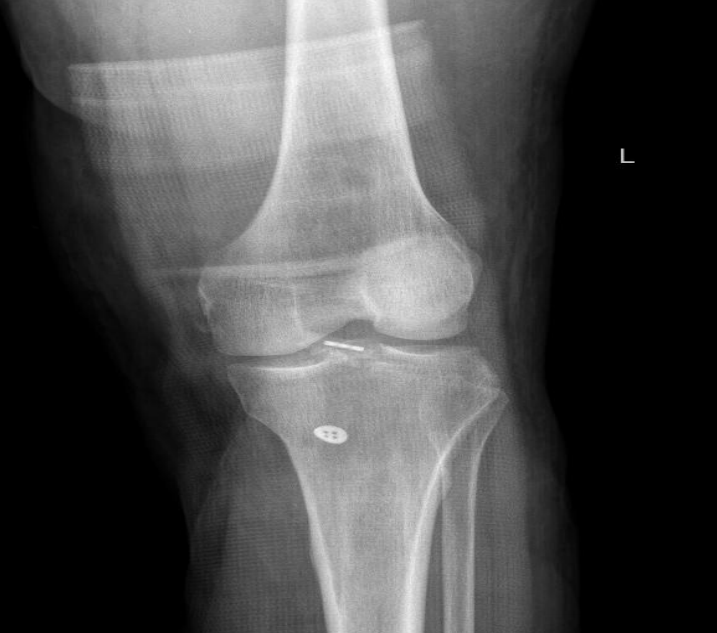

ⅢB型:多块撕脱骨折;合并半月板撕裂;BC>15mm;AE/AD≥1/2。

术式: 双袢(后叉前建立骨道)+骨道固定

合并内侧半月板放射裂

撕脱骨折、内侧半月板放射裂

半月板骨道固定、双袢固定撕脱骨折

术后X线片